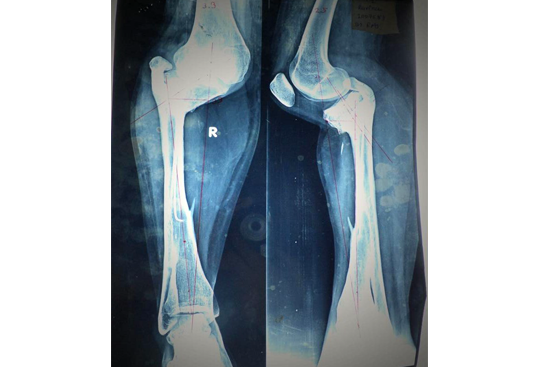

HTO Ilizarov